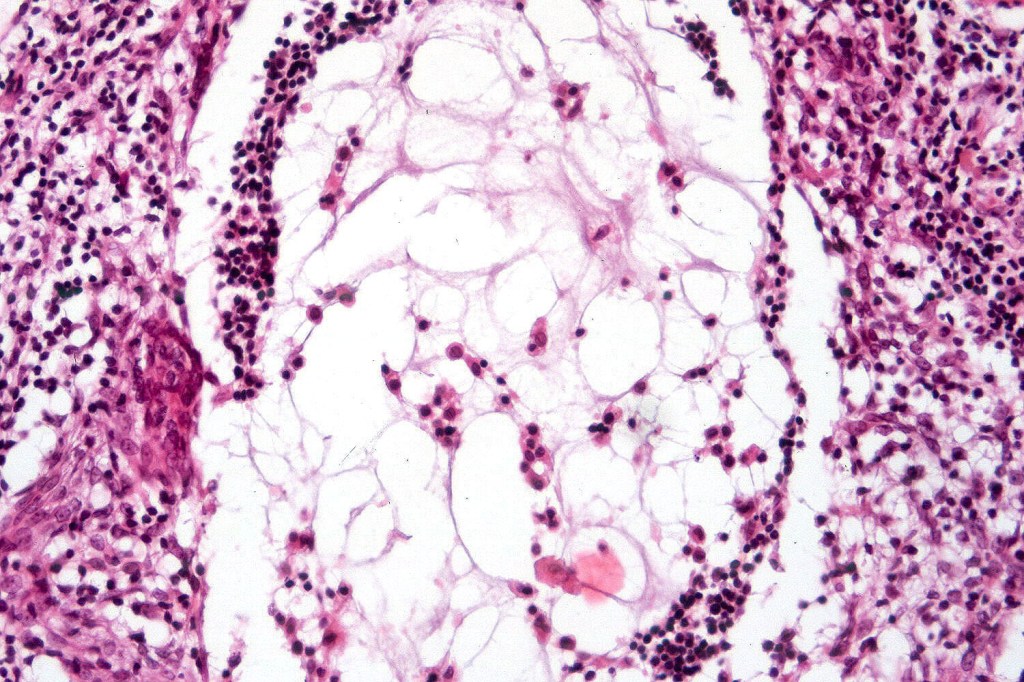

•Follicular infiltration by atypical lymphocytes & Sézary cells

•+/- mucinosis

•+/- basaloid follicular hyperplasia